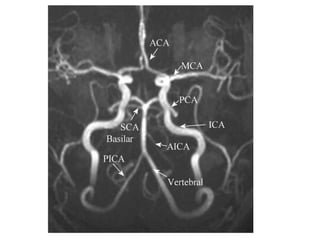

The document discusses the posterior arterial circulation of the brain, including the arteries that supply blood to the brainstem and cerebellum. It outlines the main arteries - the vertebral arteries, basilar artery, posterior inferior cerebellar artery (PICA), and anterior inferior cerebellar artery (AICA) - and describes their segments and typical vascular territories. The document also notes there can be variations in the anatomy of these arteries and lists some references for further information.